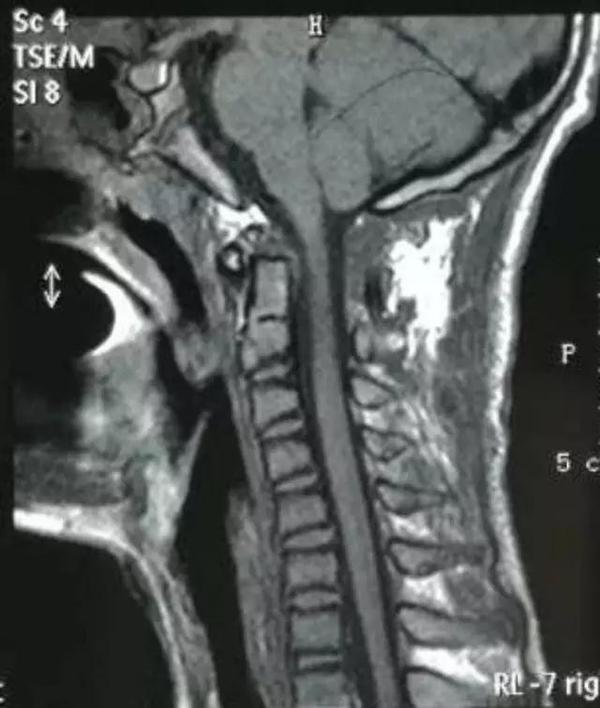

术后影像资料

2、术后复查见复位满意,脊髓减压充分,颈脊角纠正满意。

4、采用Goel技术治疗寰枢椎脱位,短节段固定融合,枕颈活动丢失较小,术后发生断钉断棒风险小,在一定程度上优于枕颈融合复位固定手术。